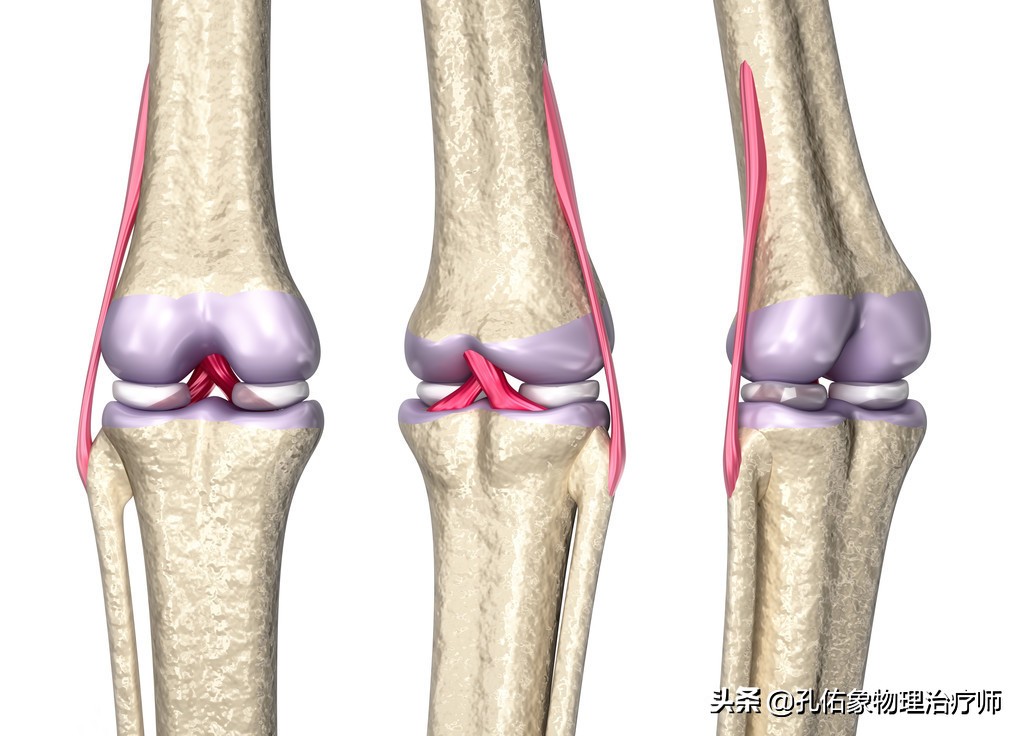

半月板的解剖结构特点

它位于膝关节大腿骨和小腿骨的软骨面之间,半月板在膝关节的内外侧各有一块,它是纤维软骨。其表面是非常光滑的,有一定的弹性。在膝关节屈伸活动的时候,可以帮助膝关节更好的匹配自由运动;同时增加了胫股关节之间的接触面积,减少局部的压力而分担身体的负荷,减少了大腿骨和小腿骨上关节软骨在膝活动时候所承受的摩擦,起着保护膝关节稳定的功能。

如上图所示,是膝关节水平面从上往下看的一个剖面图,前方有前交叉韧带,后方有后交叉韧带,在胫骨平台里面有内侧的半月板和外侧的半月板,前方称为半月板的前角(绿色),后方称为半月板的后角(紫色),不管是内侧半月板还是外侧半月板都有前后角,连接前后角的中间部分是半月板体(红色);所以经常会在膝关节损伤时拍核磁共振显示:半月板的前角损伤,后角损伤或是撕裂,指的就是这些地方,在您脑子里就会有这个映像,因为半月板是我们没办法去用手可触及到的,在外观上,我们也不能用肉眼去看到。